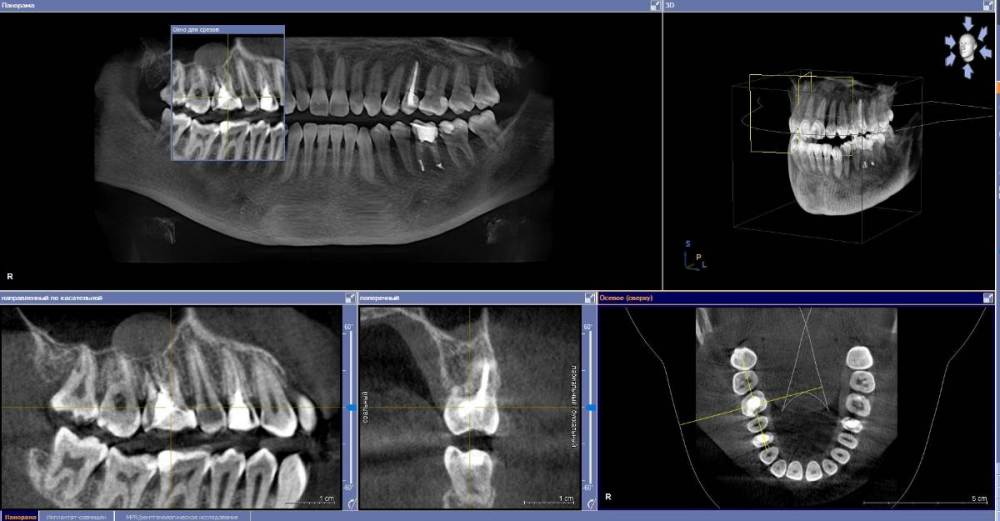

anishuma Опубликовано 1 сентября, 2021 Поделиться Опубликовано 1 сентября, 2021 (изменено) Здравствуйте, прошу помочь разобраться с моими КТ и направить для дальнейших действий. История такая: в 2018 году шестой зуб сверху справа был депульпирован. Долго сохранялись боли при нажатии, при жевании, зуб реагировал на холодной и горячее. Врач, который лечил, заверила что это постпломбировочные боли и скоро пройдет. Коронку побоялась ставить из-за этих болей. Затем примерно через год отлетел кусочек пломбы. Зуб восстановили для дальнейшей установки коронки. На данный момент есть ощутимая реакция на давление, при жевании, при чистки зубной щеткой. Зуб реагирует на холодное-горячее. Один врач сказал, что не видит показаний для перелечивания каналов. Другой врач настаивает на удалении зуба. Подскажите, пожалуйста, где истина, и возможно ли сохранить зуб. Изменено 1 сентября, 2021 пользователем anishuma Ссылка на комментарий

Bier Опубликовано 2 сентября, 2021 Поделиться Опубликовано 2 сентября, 2021 похоже что есть гранулема на корне 2 Ссылка на комментарий

St. Опубликовано 3 сентября, 2021 Поделиться Опубликовано 3 сентября, 2021 +1 к гранулеме. Я бы перелечивала каналы. Но нужно в процессе будет смотреть нет ли трещин в корне. Ссылка на комментарий